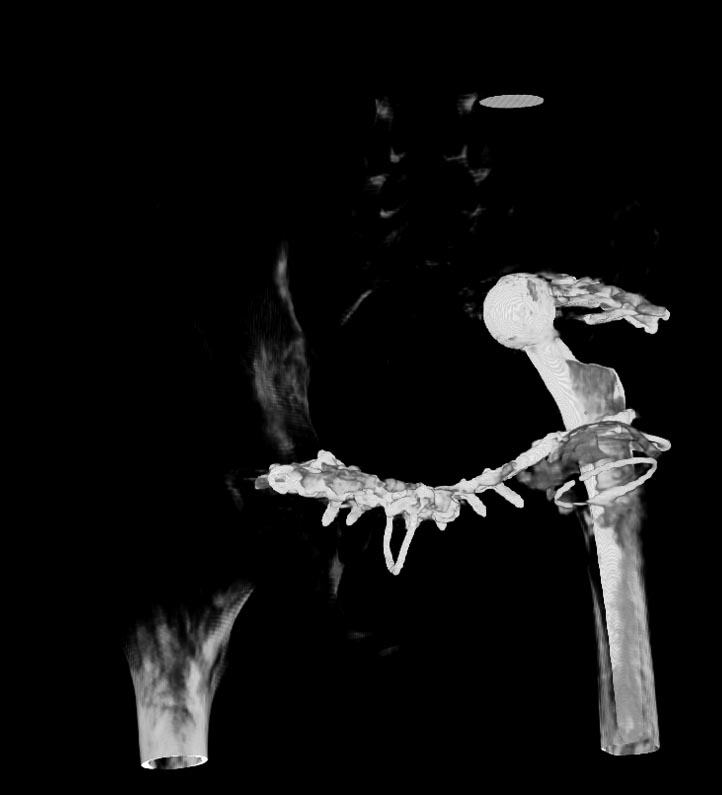

Мужчина 21 год, 2 года назад обнаружен эхиннокок костей таза, часть костей удалена сделано эндопротезирование и остеосинтез. Послеоперациооный период протекал гладко, через 6 месяцев упал, лечился консервативно, далее цепная реакция из проблем: гнойный остеомилит, свищи и лизис костей таза, на бак посеве эхинокок не обнаружен. Бедро не опорно, но больной предвигается на костылях. Картина маслом на рентгене и кт.об артродезировании думали, но диастаз большой, да и на фоне лизиса и остеопороза?????